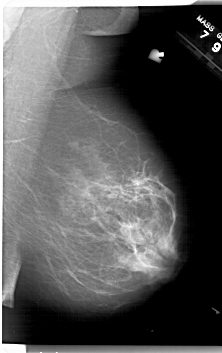

A_1626_1.RIGHT_CC

RIGHT_MLO LINES 6706 PIXELS_PER_LINE 4216 BITS_PER_PIXEL 12 RESOLUTION 43.5 NON_OVERLAY